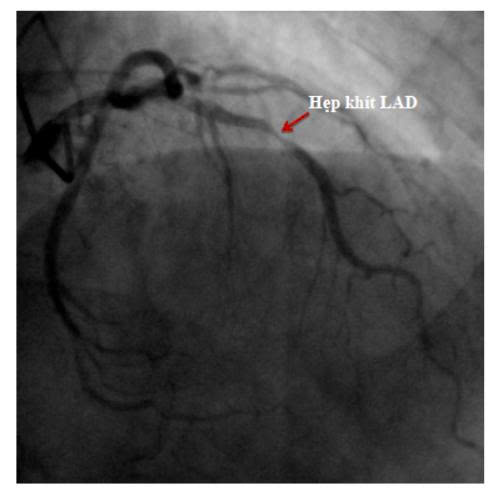

Nhiều bệnh nhân không có cơn đau tim rõ ràng, chỉ cảm thấy mệt, hụt hơi, tức ngực thoáng qua.

Tuy nhiên, khi kiểm tra chuyên sâu, bác sĩ phát hiện hẹp nặng động mạch vành LAD – nhánh mạch quan trọng nuôi tim.